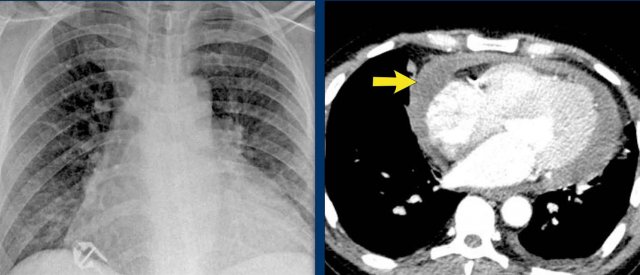

Pericardial effusion

When encountering an enlarged cardiac silhouette on chest radiography, it is essential to consider pericardial effusion as a potential mimic of cardiomegaly.

Case Example 1: Pericardial Effusion Mimicking Cardiomegaly

• On the chest radiograph, the patient appears to have a dilated heart.

• However, CT imaging clearly demonstrates that the apparent enlargement is due to significant pericardial fluid accumulation, not true myocardial chamber enlargement.

Case Example 2 - CT imaging

• CT imaging revealed a large posterior pericardial effusion compressing the left ventricle (blue arrow: effusion; red arrow: compressed, contrast-filled left ventricle).

• Surgical exploration confirmed a large posterior pericardial hematoma.

Note

: Minimal anterior fluid on ultrasound may underestimate the true volume if the effusion is loculated posteriorly, highlighting the value of CT in postoperative cases.